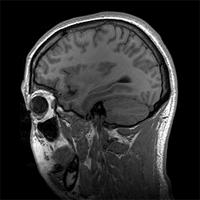

△不断进步的神经显像学技术可检测活体大脑的各种特性,但仍不能完全取代组织检测(来源:维基百科)